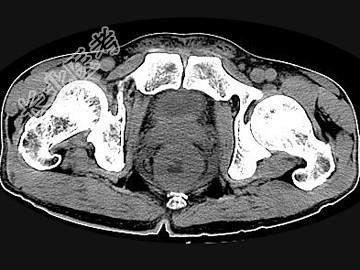

- 单项选择题男,56岁, 排便形状改变,便后不尽感, CT检查如图所示,下列说法正确的是 ( )

A、肠壁上有蒂状新生物

B、其表面光滑,边界清楚

C、肠腔未见狭窄

D、此为直肠息肉

E、此为直肠癌